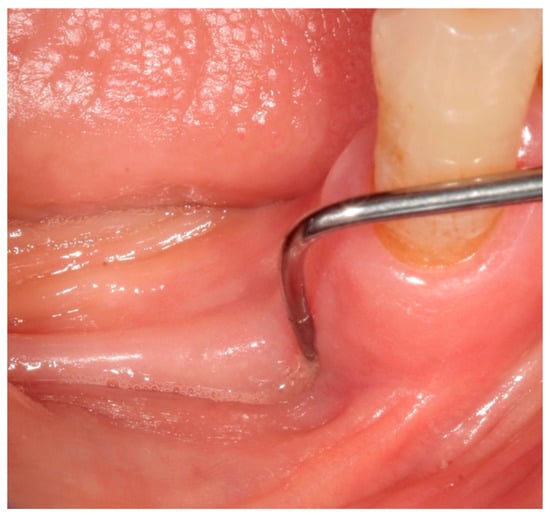

2. Case Report